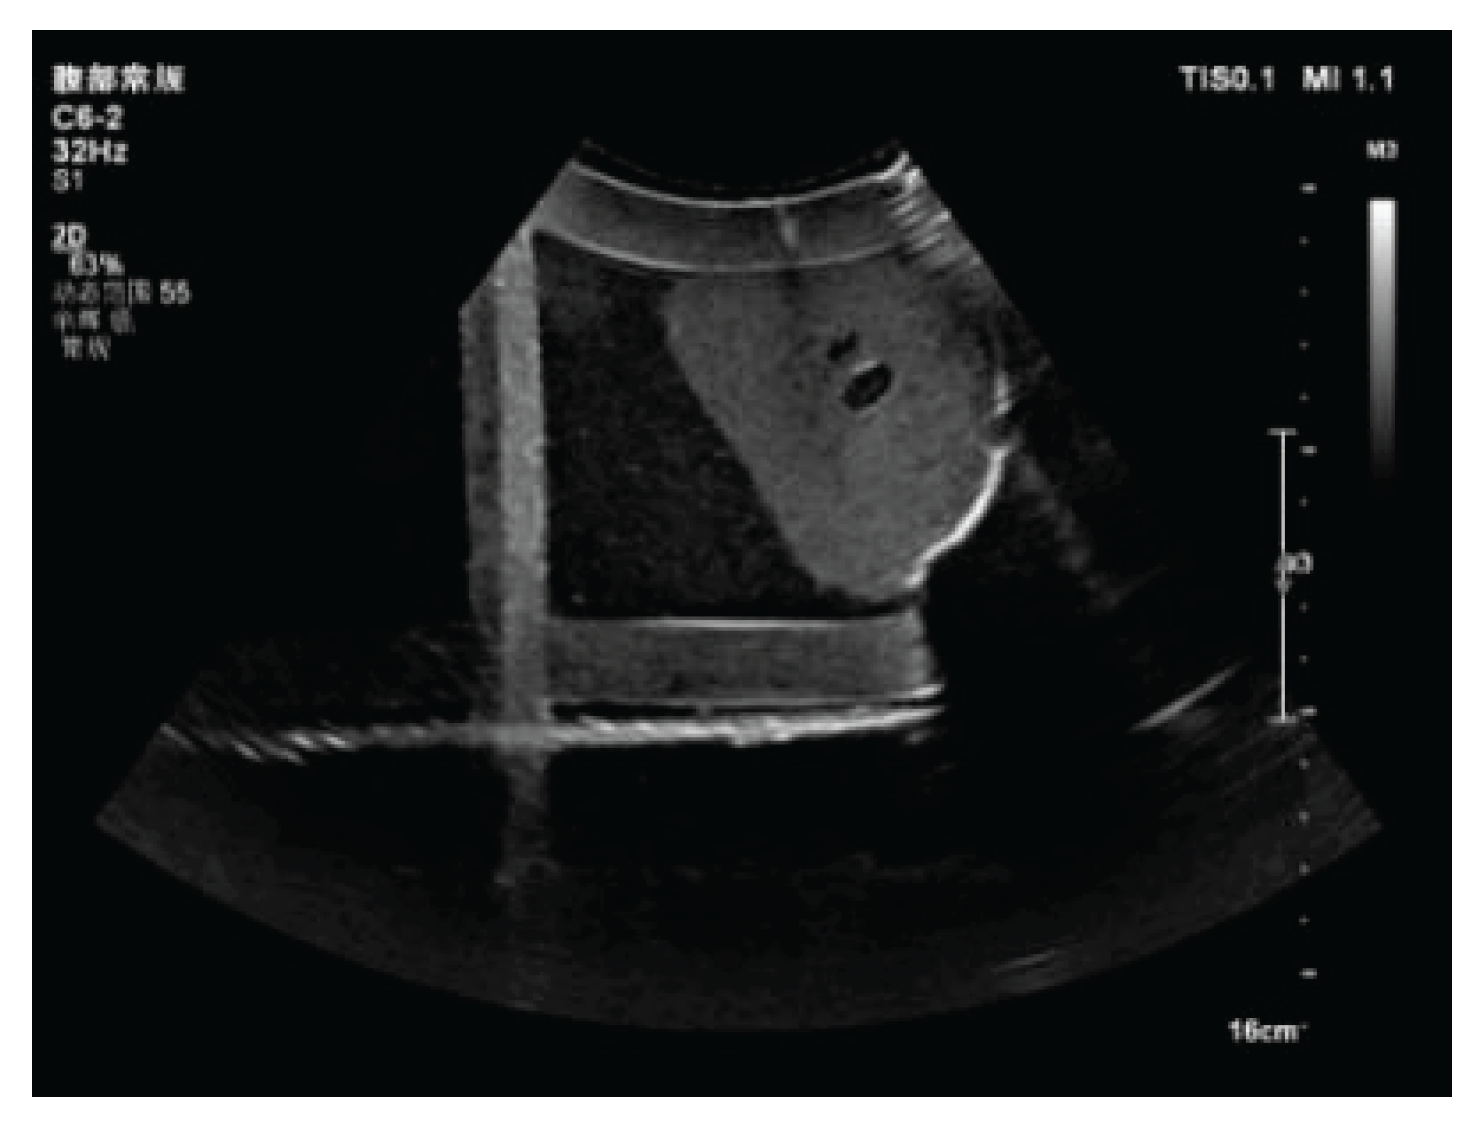

3.1. Three-Dimensional Reconstruction Results of Local Liver Ultrasound

3.2. Image Segmentation and Recognition Results